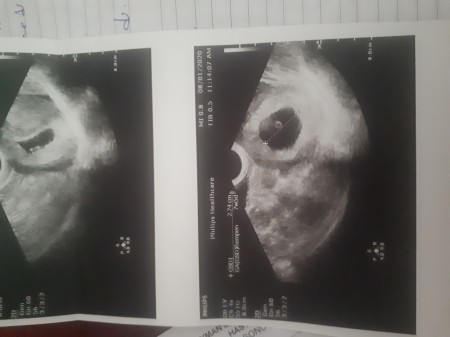

image

Ee bebis gorunuyo nasil bos der bunlar salakmi ya.tek bebek goruyorum ben  ama ikizdir insAllah

Bende anlamadım pek anlamiyorum resimlerden bir sey de bana bebek yok dedi boş gebelik ne dedikleri belli degil

Ben bos gebelik yasadim .zaten bos oldugu icin yani salikliz oldugu icin fazla ilerlemiyor.kanamam oldu dta gottim bos dedi ve kan gelmesine ramen keseye bisiy olmamis yani kendi durmez dedi kurtaj oldum.bak senin resmindeki siyahlik kese.icindeki beyaz olan bebeyin.bende sadece keseydi istersen resminide ata bilirim.3 ay sonra hamile kaldim bu kez bebeyimdr var kalp atisinida duyduk 6.7 haftalikken gottiyimde.wuan 11 haftamizi doldurucaz 1 gune .

Birde bu canim